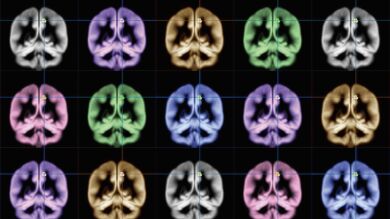

El 'rincón feliz' de tu cerebro Universidad de Kioto

Para determinar ‘el rincón feliz de nuestro cerebro’, los investigadores escanearon con resonancia magnética (MRI) a un grupo de participantes y cruzaron estas imágenes de sus cerebros con las respuestas a un cuestionario, en el que se les preguntaba si eran felices, cómo sentían sus emociones o si estaban satisfechos con sus vidas.